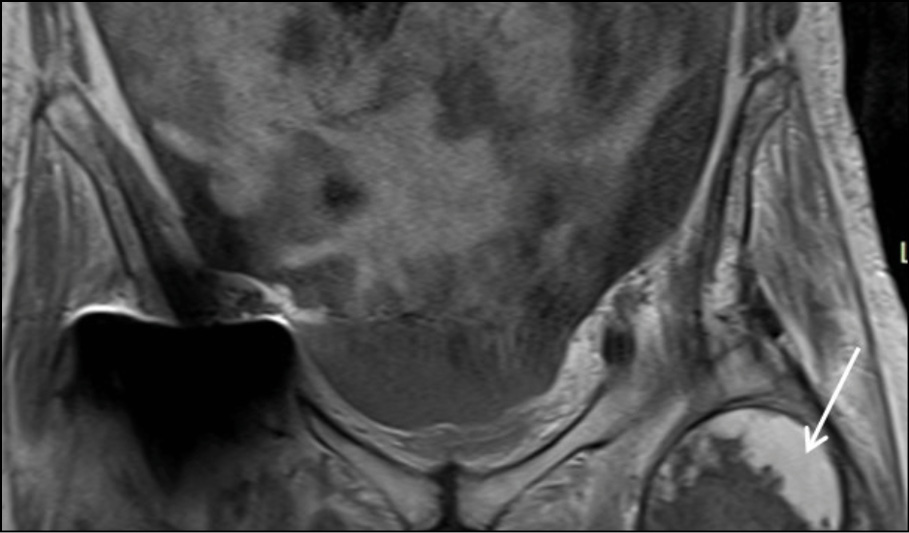

The collection exhibited heterogeneous content, peripheral enhancement, as well as solid-enhancing wall components (Figure 2c-2d). Moreover, bilateral myositis was noted in the upper thigh muscle groups, with abscess formation in the left rectus femoris and the left vastus lateralis (Figure 2e). These findings suggested the presence of an inflammatory pseudotumor following hip arthroplasty, possibly compounded by systemic bacteremia, as evidenced by a history of cat bite. Fluid accumulation was also evident in the pelvic cavity.

Figure 2e - Axial T1 post Gd Fat –Suppression image at the level of proximal femur. White arrow shows abscess formation in the left rectus femoris and the vastus laterali.